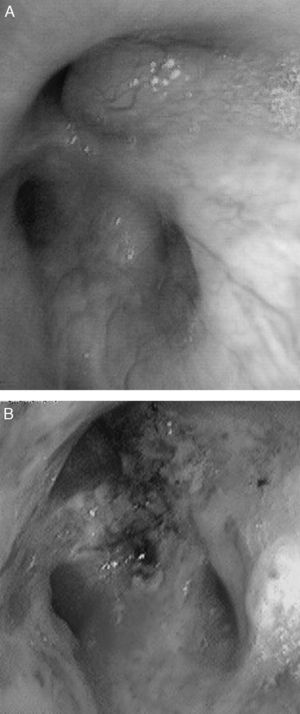

CasosCaso 1Varón de 46 años que consultó por tos no productiva, disnea de moderados esfuerzos de nueva aparición y fiebre de 38°C. Como único antecedente, fumador de 45 paquetes/año sin criterios clínicos de bronquitis crónica. En la exploración física destacaba saturación basal de oxígeno medida por pulsioximetría (SpO2) de 93% respirando aire ambiente, y en la auscultación pulmonar roncus en ambos hemitórax. La radiografía de tórax mostró una condensación alveolar en la base derecha e incipiente en el ápex izquierdo, y una imagen nodular en el segmento apical del lóbulo inferior izquierdo. En la analítica sanguínea presentaba leucocitosis de 17,6×109/l con neutrofilia del 86% y una proteína C reactiva de 19mg/dl. Ante la sospecha de neoplasia pulmonar, se realizó una tomografía computarizada (TC) de tórax que mostró imágenes en vidrio deslustrado en el lóbulo superior izquierdo y en segmentos posterobasales de ambos lóbulos inferiores, así como múltiples imágenes nodulares (centroacinares) y de árbol en brote, localizadas en el segmento apical del lóbulo inferior izquierdo y en segmentos posterobasales con tendencia a conglomerarse, sin formaciones adenopáticas. Se realizó fibrobroncoscopia, que evidenció una obstrucción >80% de la luz de los bronquios B1-B6D por infiltración de la submucosa y lesiones nodulares (fig. 1A), así como una estenosis irregular de los bronquios basales derechos. Además presentaba un ensanchamiento carineal y estenosis traqueal en el tercio superior. La biopsia mostró epitelio respiratorio con depósitos de material amiloide que, tras la realización de técnicas inmunohistoquímicas con rojo Congo, se confirmó como amiloidosis. Se realizó estudio de extensión, descartándose enfermedad sistémica, por lo que se estableció el diagnóstico de amiloidosis primaria traqueobronquial localizada.

El paciente del caso 1 fue tratado en 2 ocasiones con láser Nd:YAG para la repermeabilización de la vía aérea (fig. 1B), debido a la estenosis que presentaba por infiltración amiloide, con lo que se consiguió una mejoría clínica y funcional del paciente. En cuanto a la paciente del caso 2, recibió tratamiento con una combinación de prednisona y melfalán, con buena respuesta y resolución parcial de las lesiones traqueales sin afectación funcional ni sintomática.